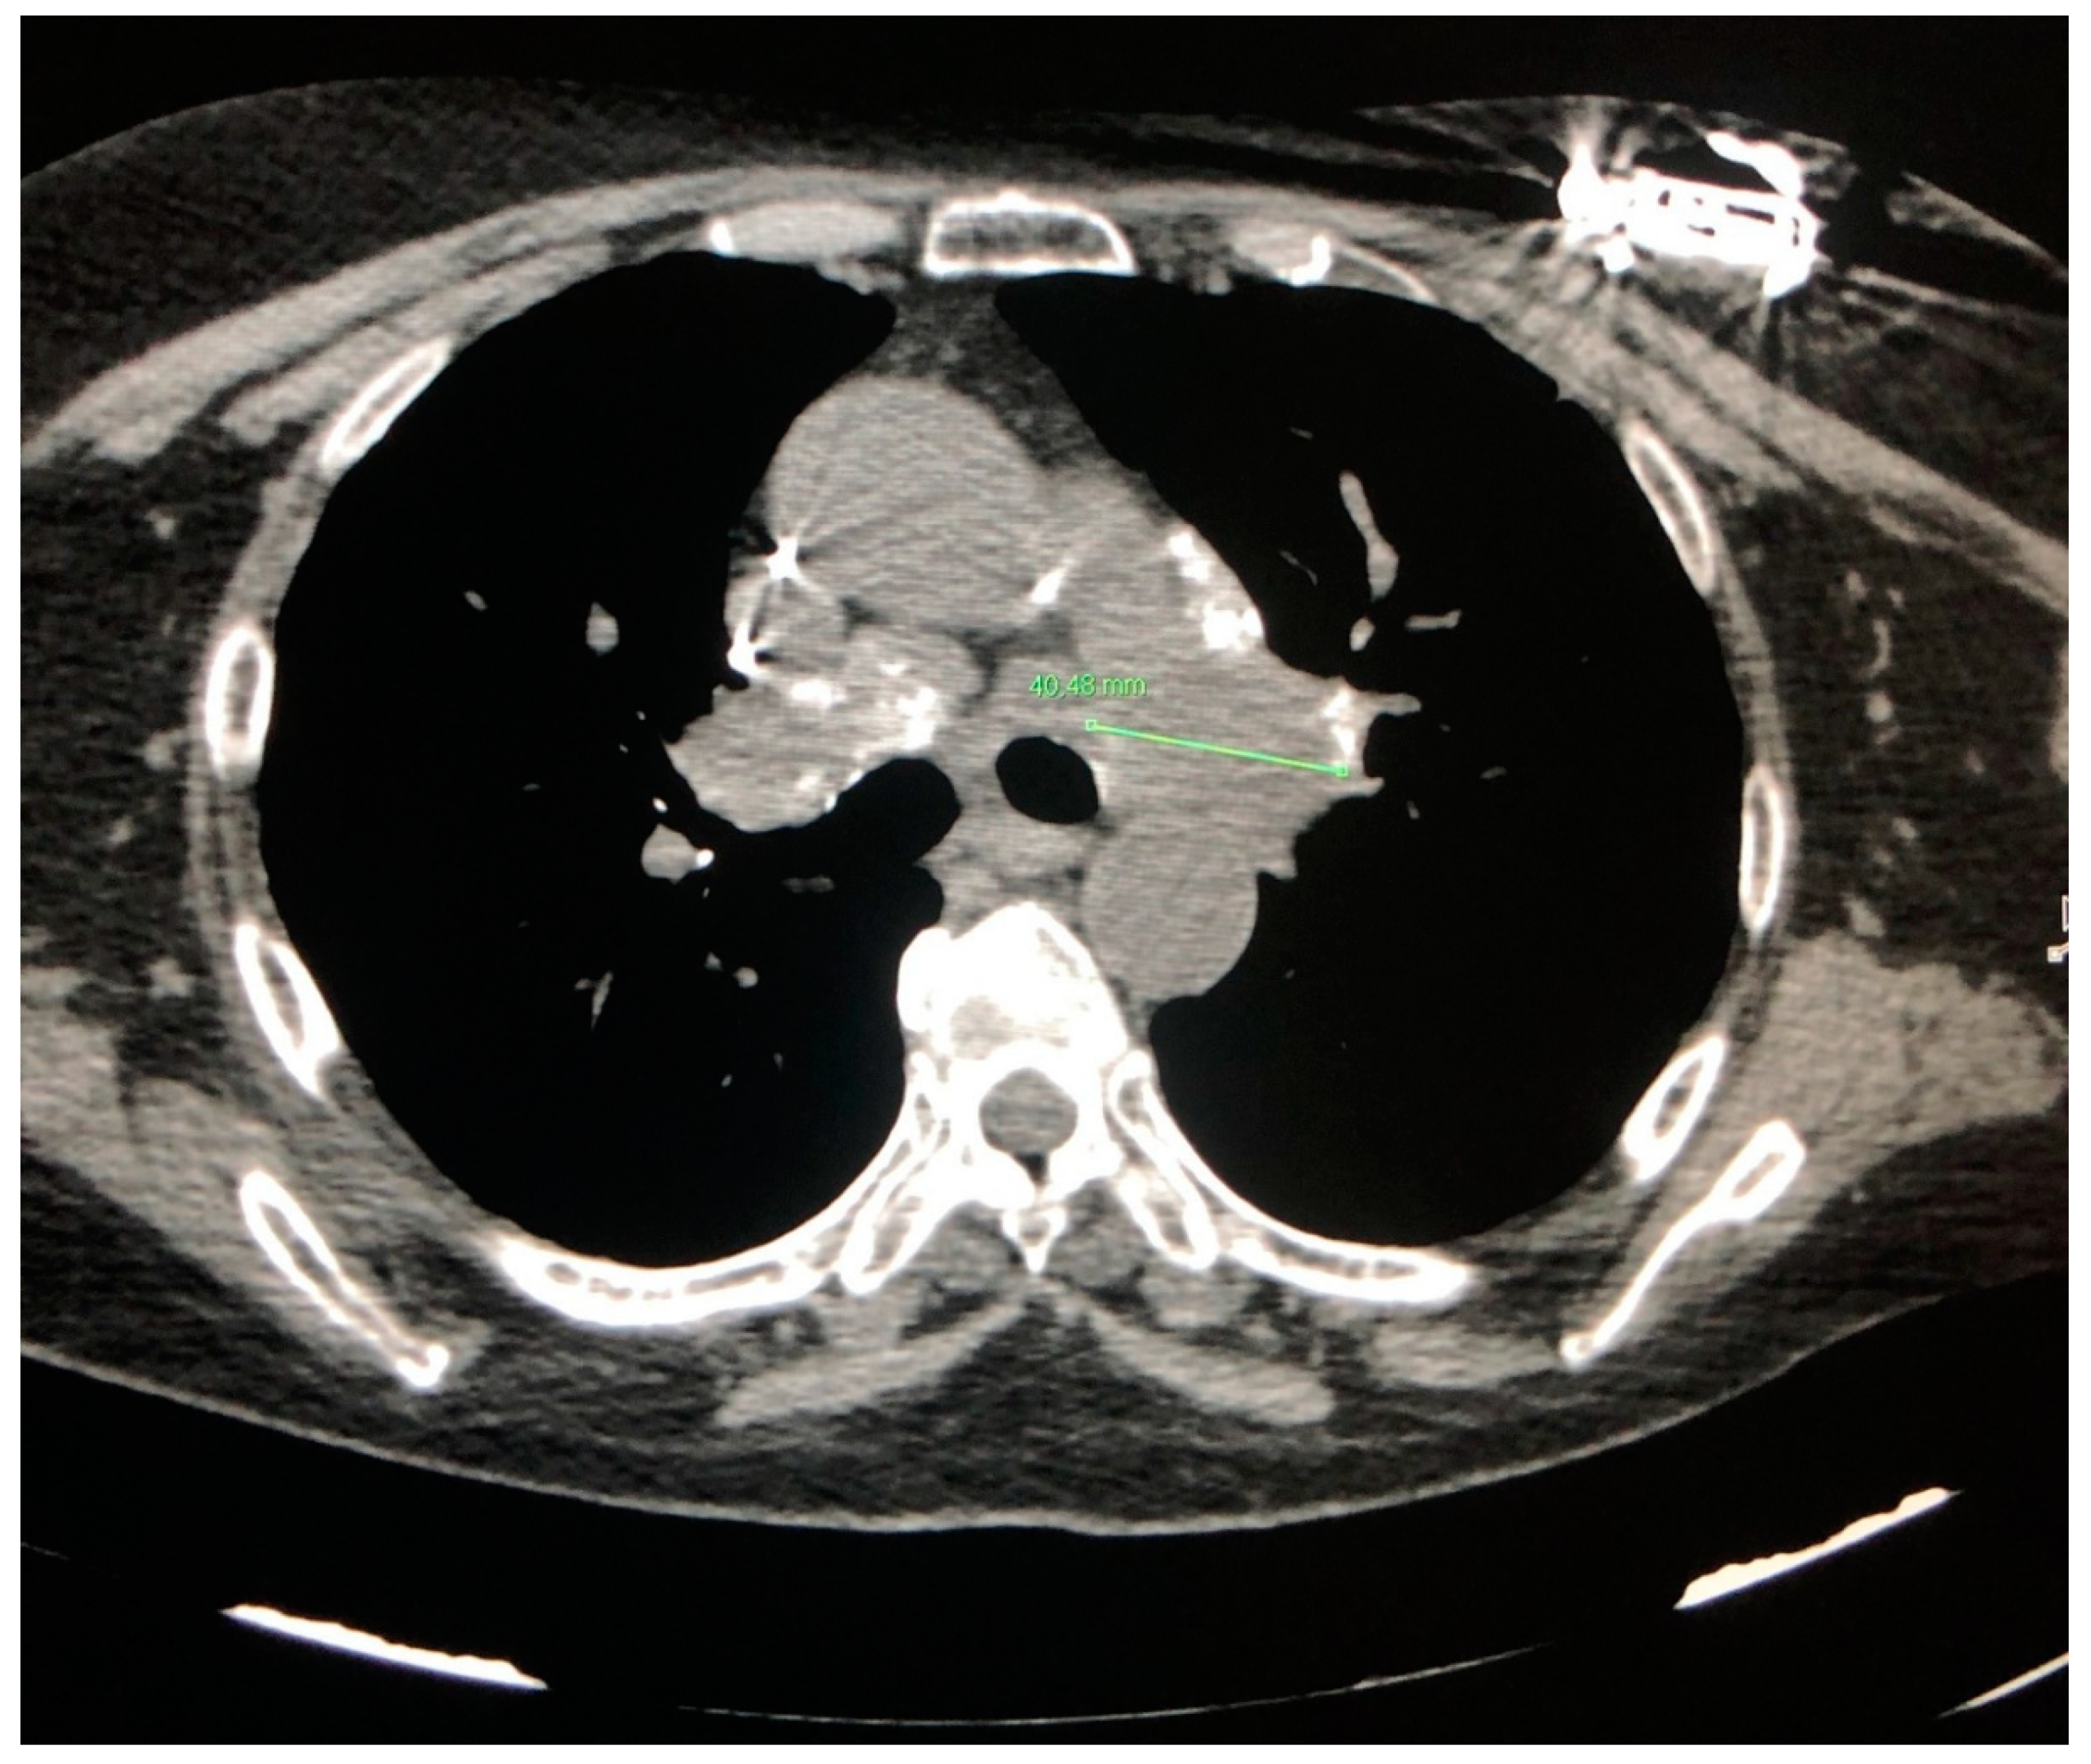

3. CT in Pulmonary Sarcoidosis, Imaging Findings and Classification